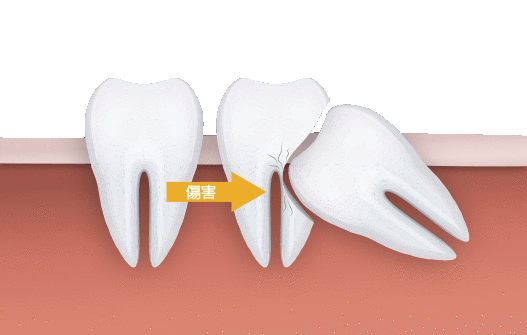

外面拔時易斷裂於骨頭內而難以取出